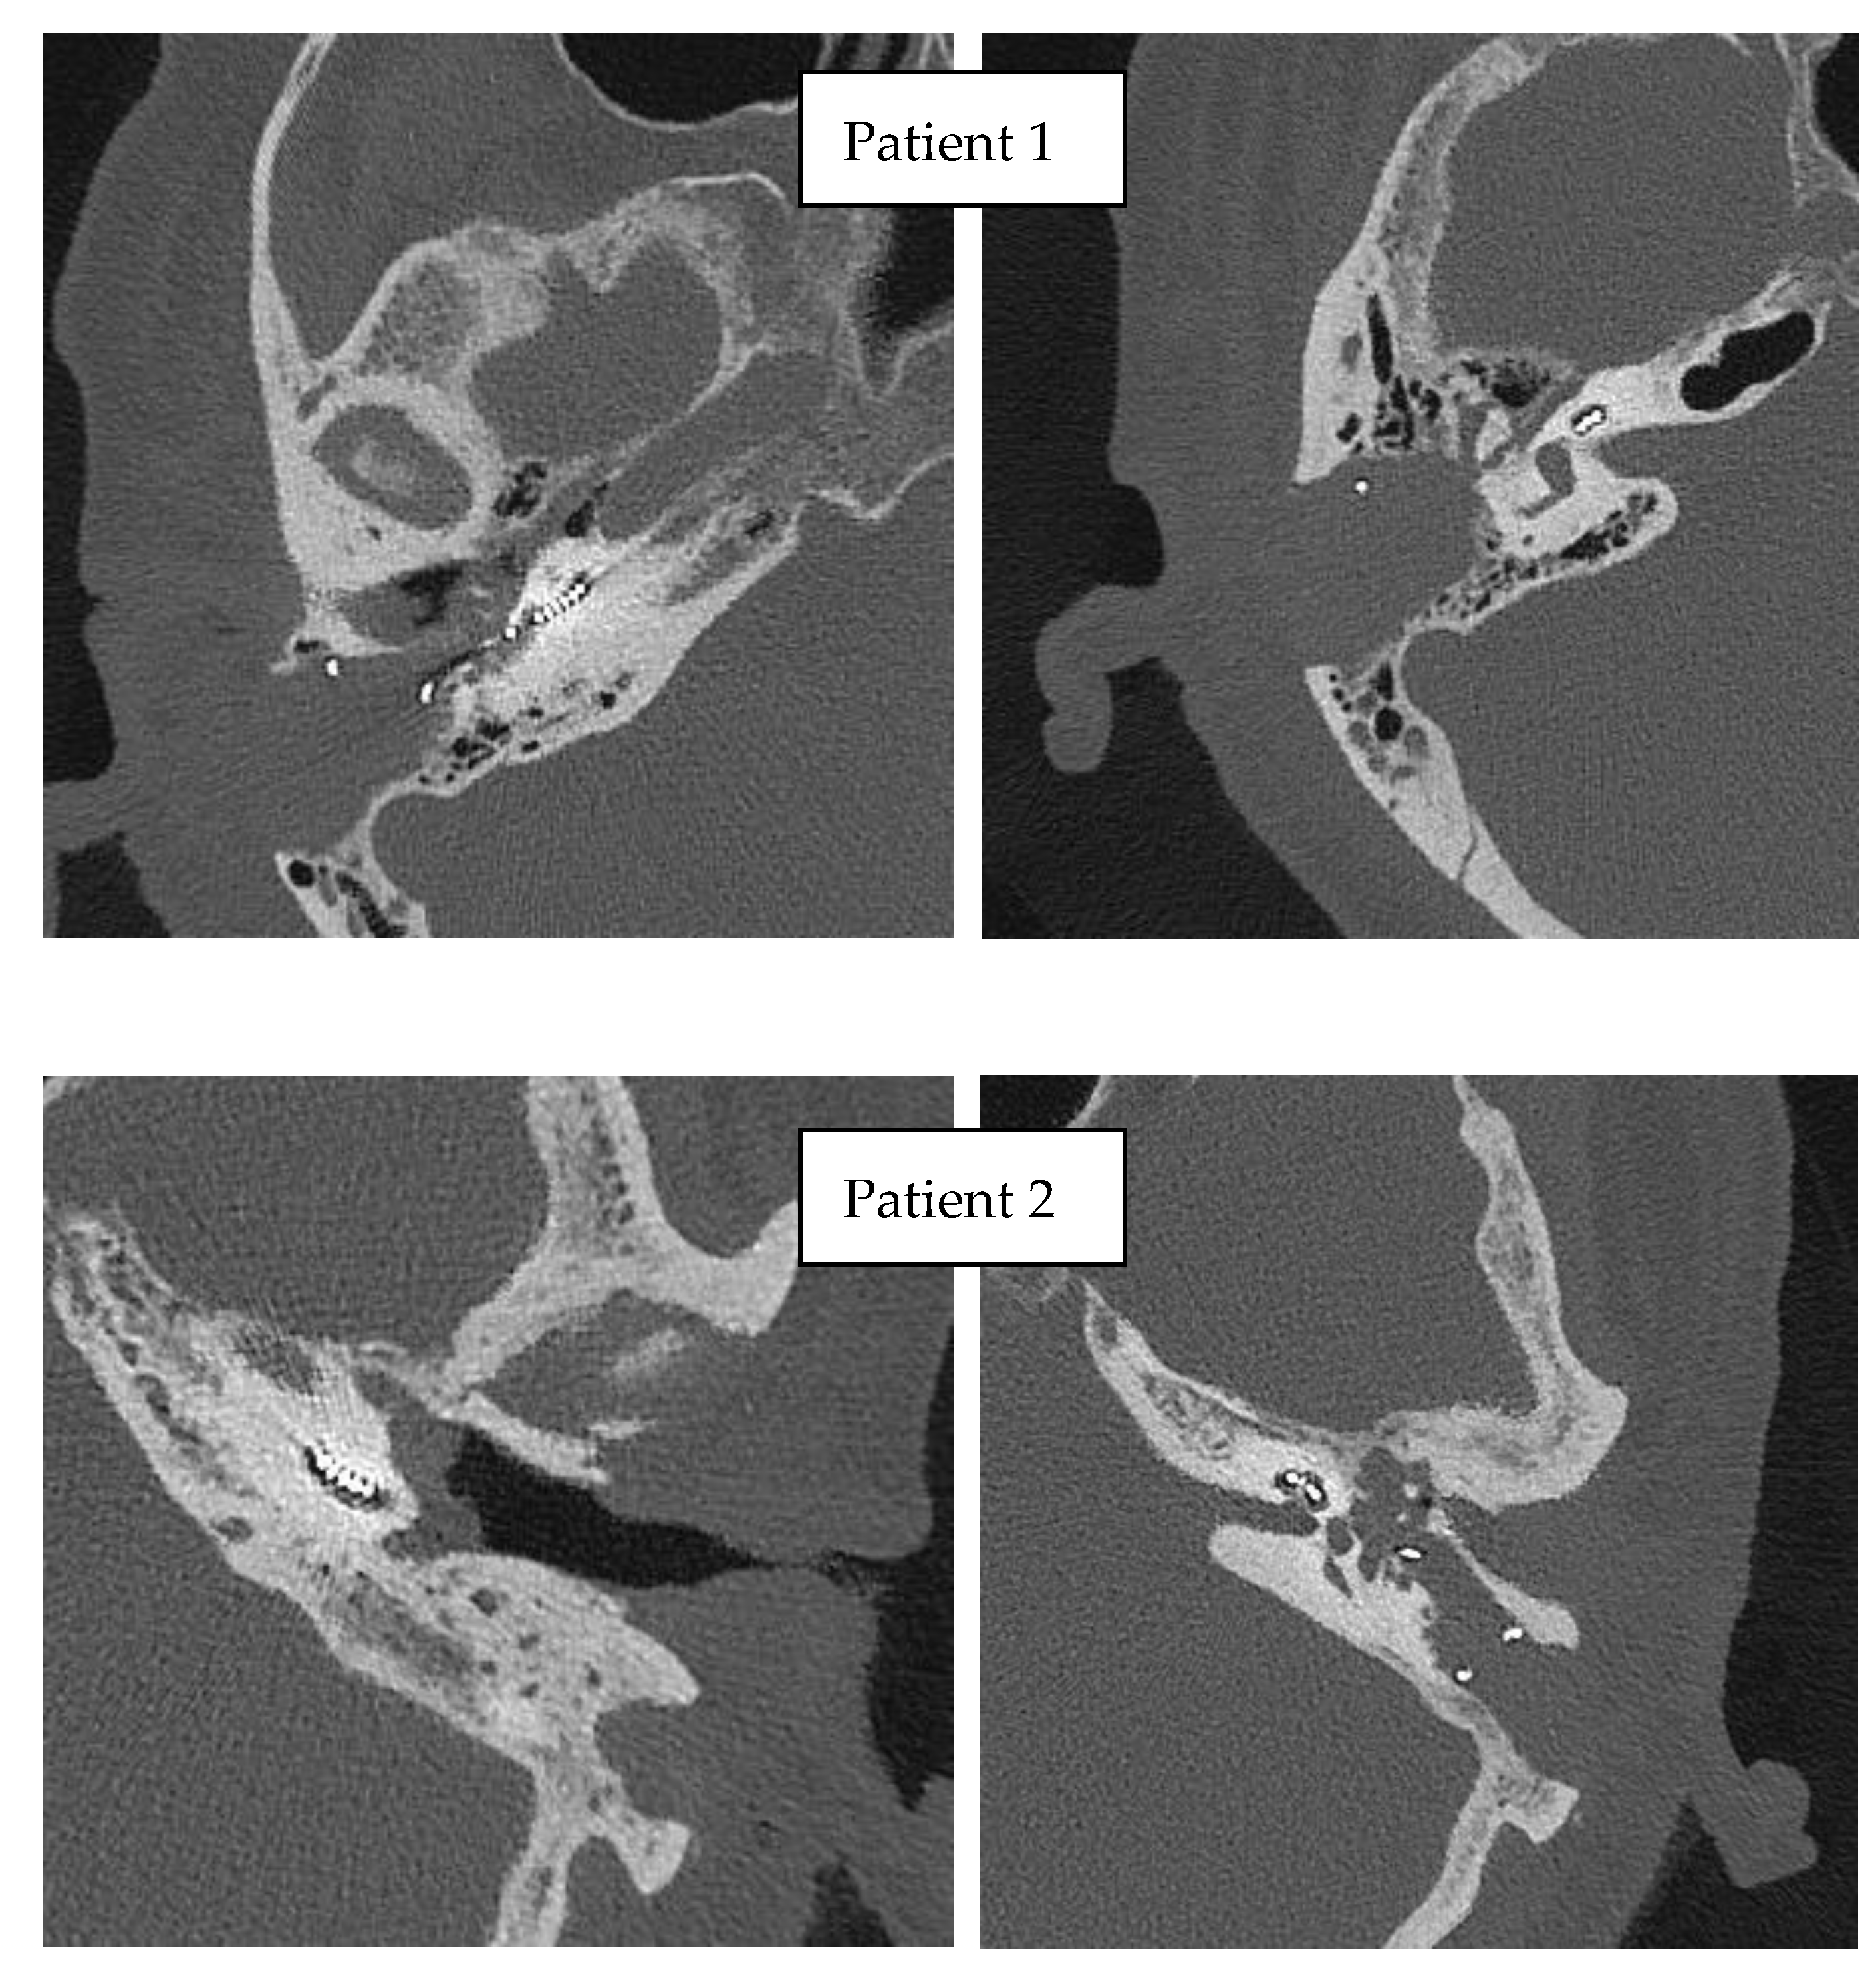

3.3. Imaging

The post-operative CT confirmed the intracochlear position of the electrode arrays (with the tip of the electrode array in the medial turn of the cochlea) in both patients (Figure 9).

Figure 9.

Postoperative CT scans of operated patients.